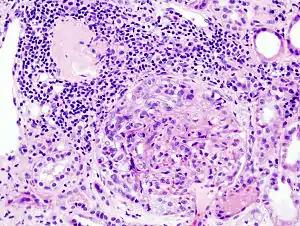

Histopathological image of crescentic glomerulonephritis in a patient with MPO-ANCA positive rapid progressive glomerulonephritis. Hematoxylin & eosin stain.

Rapidly progressive glomerulonephritis (RPGN) is a syndrome of the kidney that is characterized by a rapid loss of kidney function,[4][5] (usually a 50% decline in the glomerular filtration rate (GFR) within 3 months)[5] with glomerular crescent formation seen in at least 50%[5] or 75%[4] of glomeruli seen on kidney biopsies. If left untreated, it rapidly progresses into acute kidney failure[6] and death within months. In 50% of cases, RPGN is associated with an underlying disease such as Goodpasture syndrome, systemic lupus erythematosus or granulomatosis with polyangiitis; the remaining cases are idiopathic. Regardless of the underlying cause, RPGN involves severe injury to the kidneys' glomeruli, with many of the glomeruli containing characteristic glomerular crescents (crescent-shaped scars).[7]

It is thought that antineutrophil cytoplasmic antibodies (ANCA) interact with antigens in the cytoplasm of neutrophils to cause an early degranulation, triggering the release of lytic enzymes at the site of injury[8] and leading to the formation of glomerular crescents that consist primarily of parietal epithelial cells from Bowman's capsule and in some cases podocytes.[9]